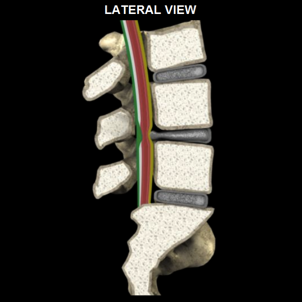

CERVICAL SPINAL STENOSIS

LUMBAR SPINAL STENOSIS

CERVICAL SPINAL STENOSIS

LUMBAR SPINAL STENOSIS